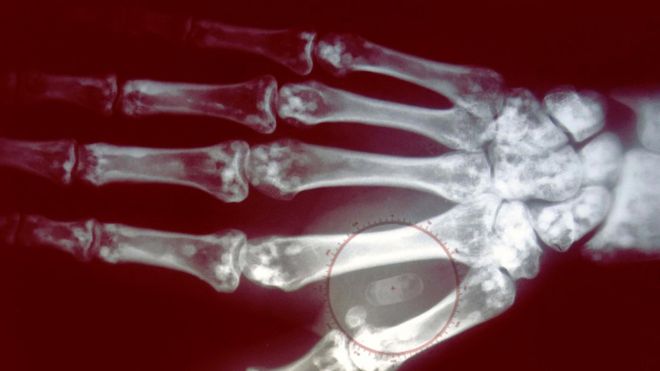

microchip

Image caption Los microchips tienen el tamaño de un grano de arroz.

microchip implantado en la mano

Image caption El microchip se coloca debajo de la piel, entre los dedos índice y pulgar.